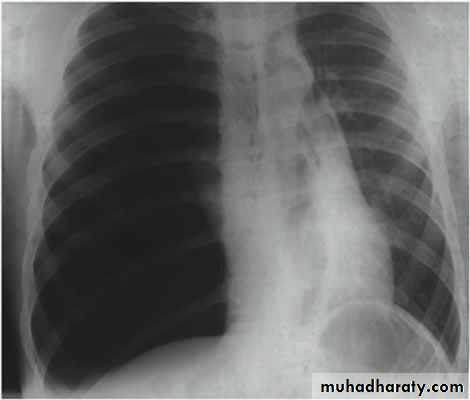

CXR:

• Signs of pleural effusion:

• Percussion: Dullness over the area of empyema